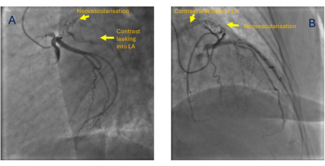

Shivam Arora, MD; Neha Chopra, MD, DM; Shitij Chaudhary, MD, DM

A 50-year-old woman presented to our center with the complaints of breathlessness on exertion for the last 2 years. On evaluation, she was diagnosed with rheumatic heart disease with severe calcific mitral stenosis.